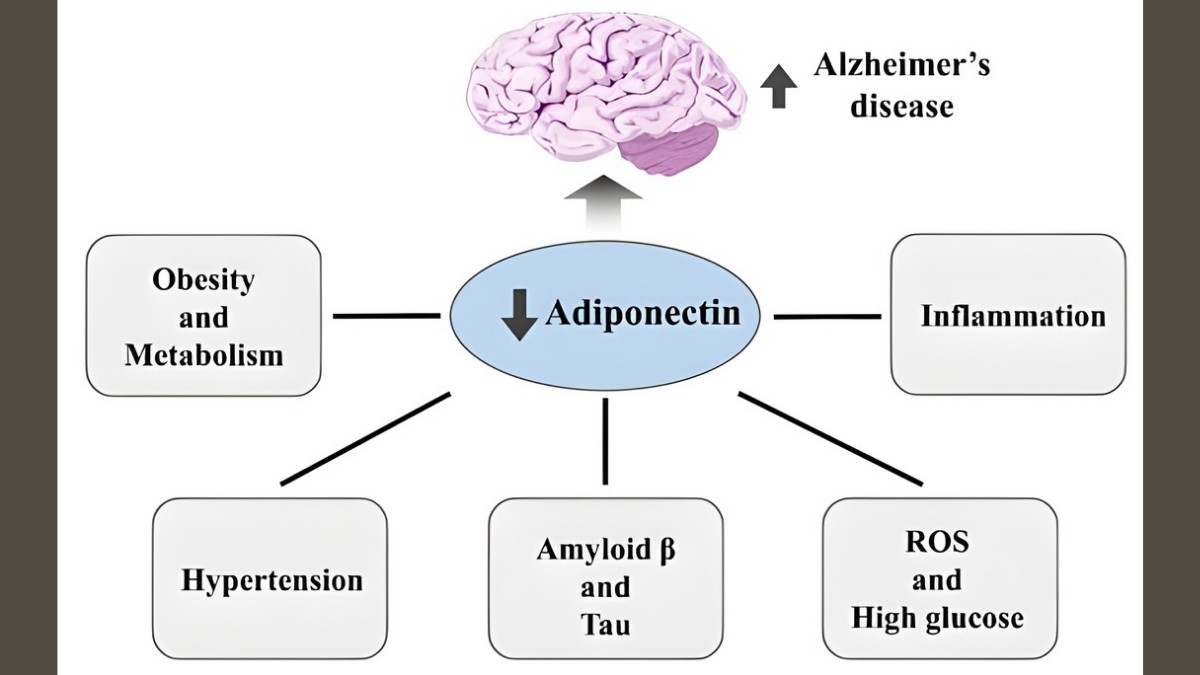

Adiponectin: The Paradox Molecule

Adiponectin seems helpful at first. At low levels, it reduces inflammation. But in OA, something changes. The joint environment turns adiponectin from friend to enemy.

In arthritic joints, adiponectin increases MMP-1 and MMP-3 production. These enzymes chew up cartilage. Research shows adiponectin correlates with aggrecan degradation—that’s the main cushioning protein in your joints breaking apart. Higher adiponectin doesn’t protect you. It makes things worse.